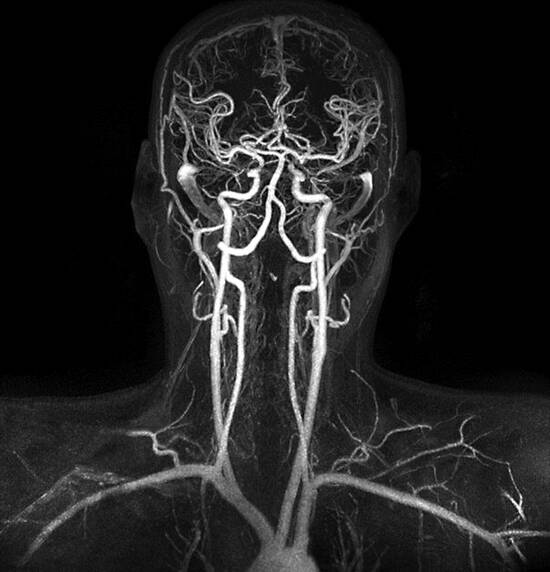

核磁共振颅脑血管造影图像

核磁共振对中枢神经系统的病灶检查具有明显的优势,对脑部肿瘤、颅内感染、脑血管病变、脑白质病变、脑发育畸形等也具有较高的诊断价值,但对颅骨折、急性脑出血以及病灶钙化并不敏感。核磁共振检查眼、鼻、喉及颈部病变也优于CT,但对这些部位的骨质病变检查不如CT。另外,核磁共振无需使用造影剂便可得到血管、胆胰管、尿路等管腔造影,而CT造影必须使用造影剂。